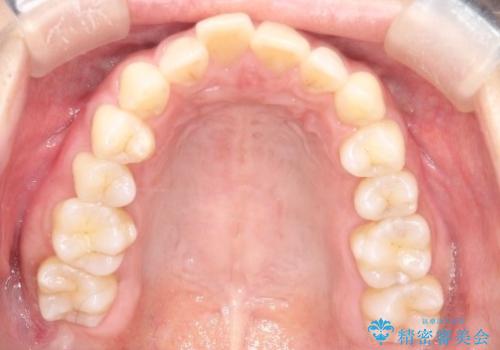

【インビザライン】前歯の凸凹を治したい

- 前歯の凸凹を主訴に来院されました。

臼歯部の遠心移動を行いながらスペースを作り、インビザラインにて前歯をきれいに並べることができました。

今回の治療計画では臼歯部の遠心移動とIPRを行っています。